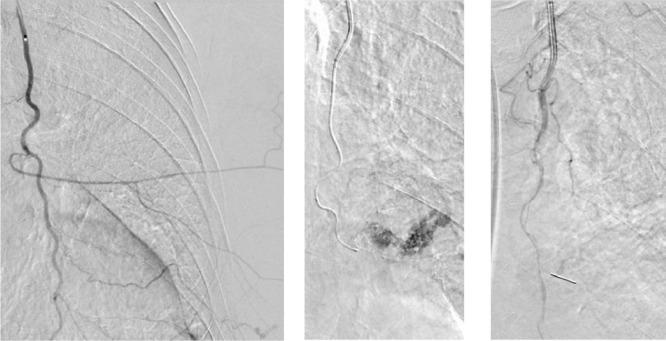

The most clinically significant complication associated with stereotactic core needle biopsy of the breast is hematoma formation, which only occurs in less than 1% of biopsies and may require treatment. Cases of uncontrollable bleeding, refractory to repeated compression, resulting from biopsy are exceedingly rare. We present a case of catastrophic, uncontrollable bleeding and large hematoma formation resulting from stereotactic vacuum-assisted breast biopsy of a breast mass identified in screening mammography. Percutaneous embolization was planned and guided using 3D reconstructions from computed tomographic angiography, and bleeding was successfully controlled with micro-coil embolization.

与乳腺立体定向真空辅助活检相关的最具临床意义的并发症是血肿形成,其仅发生在不到1%的活检病例中,可能需要治疗。活检导致的无法控制的出血,经反复压迫仍难以控制的情况极为罕见。我们报告一例因乳腺钼靶筛查发现的乳腺肿块进行立体定向真空辅助乳腺活检后出现灾难性、无法控制的出血和巨大血肿形成的病例。计划采用计算机断层血管造影的三维重建进行经皮栓塞引导,并通过微线圈栓塞成功控制了出血。